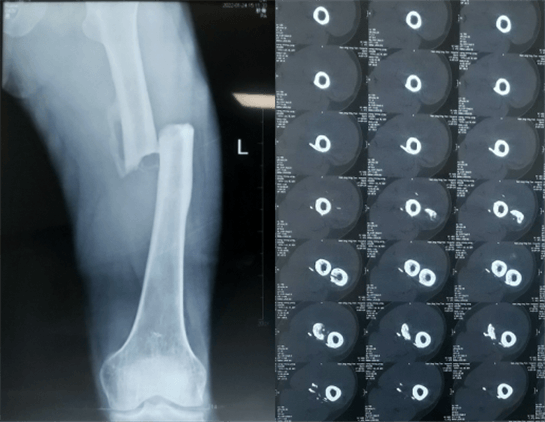

患者:男性,43歲,左股骨干骨折髓內(nèi)釘內(nèi)固定術(shù)

醫(yī)院:南京應(yīng)天骨科醫(yī)院

股骨是下肢的主要負(fù)重骨,有其特殊的解剖關(guān)系,周?chē)∪獍l(fā)達(dá),因此一旦股骨干骨折后如果治療不當(dāng),容易造成肌肉牽拉,導(dǎo)致畸形和功能障礙。治療股骨干骨折,必須遵循恢復(fù)肢體的長(zhǎng)度及力線,無(wú)旋轉(zhuǎn),盡量行以微創(chuàng),保護(hù)骨折局部血運(yùn),促進(jìn)愈合。髓內(nèi)釘對(duì)骨折的固定能夠達(dá)到較大的穩(wěn)定性和堅(jiān)固性,可以減少醫(yī)源性污染,減少軟組織分離及周?chē)┢茐?,有利于骨折早期愈合,是治療股骨干骨折的首要治療方法?/span>

術(shù)前檢查